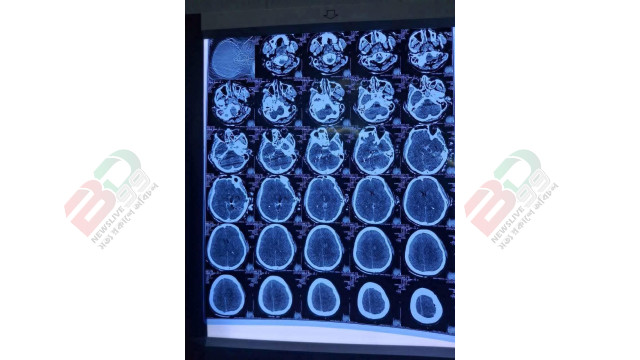

পরে হাদিকে সিপিআর দেওয়া হলে এখন একটু প্রেসার ভালো আছে। পরে তার মাথার সিটিস্ক্যান করলে কানের পাশে মাথার ভেতরে গুলি রয়েছে বলে দেখা যায়- তাকে নিউরোসার্জারি ওটিতে নেওয়া হয়েছে।

তার মাথার ভেতরে গুলি রয়েছে এবং কানের আশপাশে গুলি লেগেছে। তাকে নিউরোসার্জারি বিভাগের অপারেশন থিয়েটারে নেওয়া হয়েছে, যেখানে অস্ত্রোপচার চলছে।